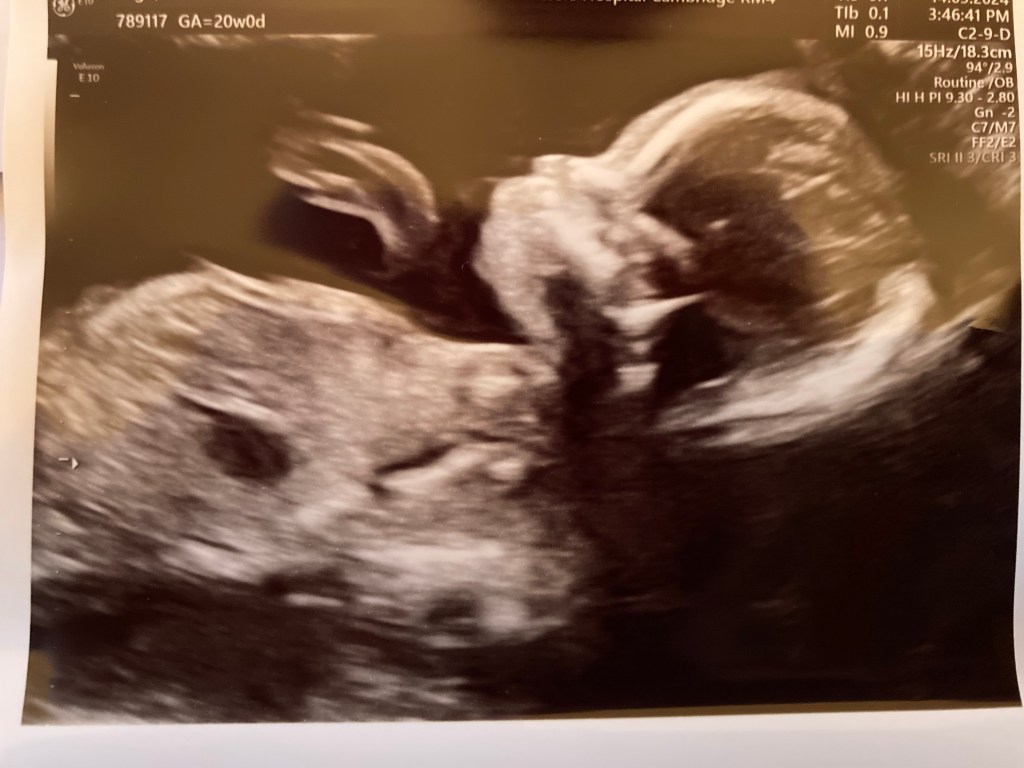

I’ve waited quite a long time to tell you, and when I say it’s because I wanted to get to the 20 week anomaly scan, you’ll probably understand why.

Yes, I tried again. I had another round of IVF, and I’m pregnant. And the baby has passed their anomaly scan with flying colours! Perfect heart, perfect stomach and diaphragm and spinal and skull and everything. One healthy, happy, wriggly little baby girl, growing rapidly and already beginning to make herself felt with little pokes and prods.